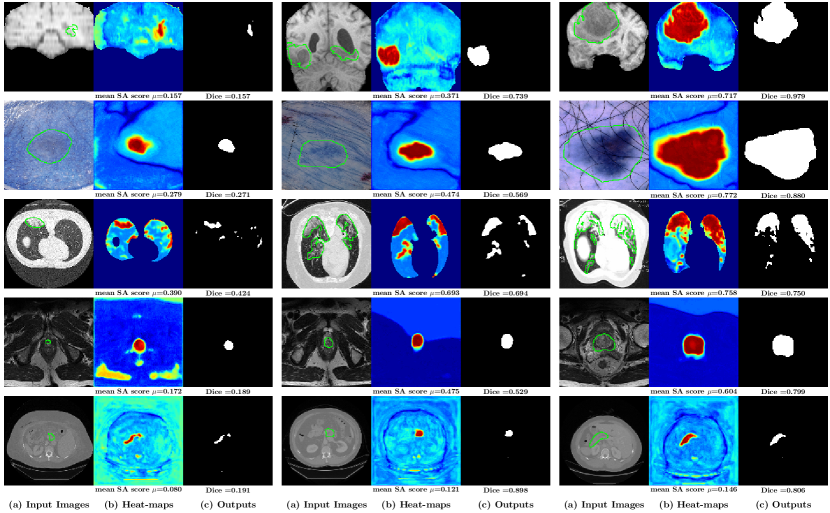

Figure 14: Examples of different input images on the ISIC dataset. The separableness is: (a) << (b) << (c).

Refer to caption

Figure 15: The scatter plot of the Dice score of the neural network versus the Dice score of segmentation map on the input image on different datasets.

The separablenesses of the input images is defined as the segmentation ability of the input images by the color/intensity values directly. For example, the image in Fig. 14(a) has a lower separablenesses since the color values on the object regions are quite similar to the color values on the normal regions. It is hard to segment such lesions, even by human experts. However, the image on Fig. 14(c) has the largest separablenesses because color values on the lesion regions (the object) are quite different from the color values on the normal regions (the background).

The separableness is considered as the special segmentation ability of the input image, which can also be computed by the proposed ProtoSeg method. The segmentation map 𝒮xsubscript𝒮𝑥\mathcal{S}_{x} can be computed by considering the colors/intensities of input image x𝑥x as features. Thus, the performance of the segmentation map 𝒮xsubscript𝒮𝑥\mathcal{S}_{x} indicates the quality or the separableness of the input image. Lesions in some images have high contrast and clear boundary, which are easy to be segmented, even using traditional methods based on color or intensity values, yielding a SAM with a high SA score.

In this section, we study the relationship of performance between the 𝒮xsubscript𝒮𝑥\mathcal{S}_{x} (the segmentation map computed directly on input image x𝑥x) and the network’s output (x)𝑥\mathcal{B}(x), investigating how neural networks improve the segmentation on each individual image x𝑥x. Fig. 15 shows the relationship between the segmentation map of input image 𝒮xsubscript𝒮𝑥\mathcal{S}_{x} and the corresponding output of the neural network (x)𝑥\mathcal{B}(x). In most cases, U-net can improve the segmentation performance and the Dice score of the output (x)𝑥\mathcal{B}(x) is higher than the SA score of 𝒮xsubscript𝒮𝑥\mathcal{S}_{x}. We define the distance between the Dice scores of the 𝒮xsubscript𝒮𝑥\mathcal{S}_{x} and (x)𝑥\mathcal{B}(x) on one image as: d=Dice(,G)SA score(𝒮x,G)𝑑Dice𝐺SA scoresubscript𝒮𝑥𝐺d=\text{Dice}(\mathcal{B},G)-\text{SA score}(\mathcal{S}_{x},G) where G𝐺G is the ground-truth. For one dataset, we compute the average distance over all possible test images as: m(d)=d/N𝑚𝑑𝑑𝑁m(d)=\sum d/N. A high m(d)𝑚𝑑m(d) means a large gain obtained by training a deep network for segmentation. Table 3 shows the Dice scores of the 𝒮xsubscript𝒮𝑥\mathcal{S}_{x}, \mathcal{B} and the m(d)𝑚𝑑m(d) on different datasets. The most challenging dataset among the five datasets is the COVID segmentation, which has the lowest m(d)𝑚𝑑m(d), indicating that the gain achieved by the trained U-Net is low. In addition, we have found that most images on BraTS and ISIC are easy samples in which the lesion regions can be easily separated only based on the input image pixels, yielding higher SA scores of 𝒮xsubscript𝒮𝑥\mathcal{S}_{x}. Thus, our proposed method can be used to describe the characteristics of the dataset for segmentation.